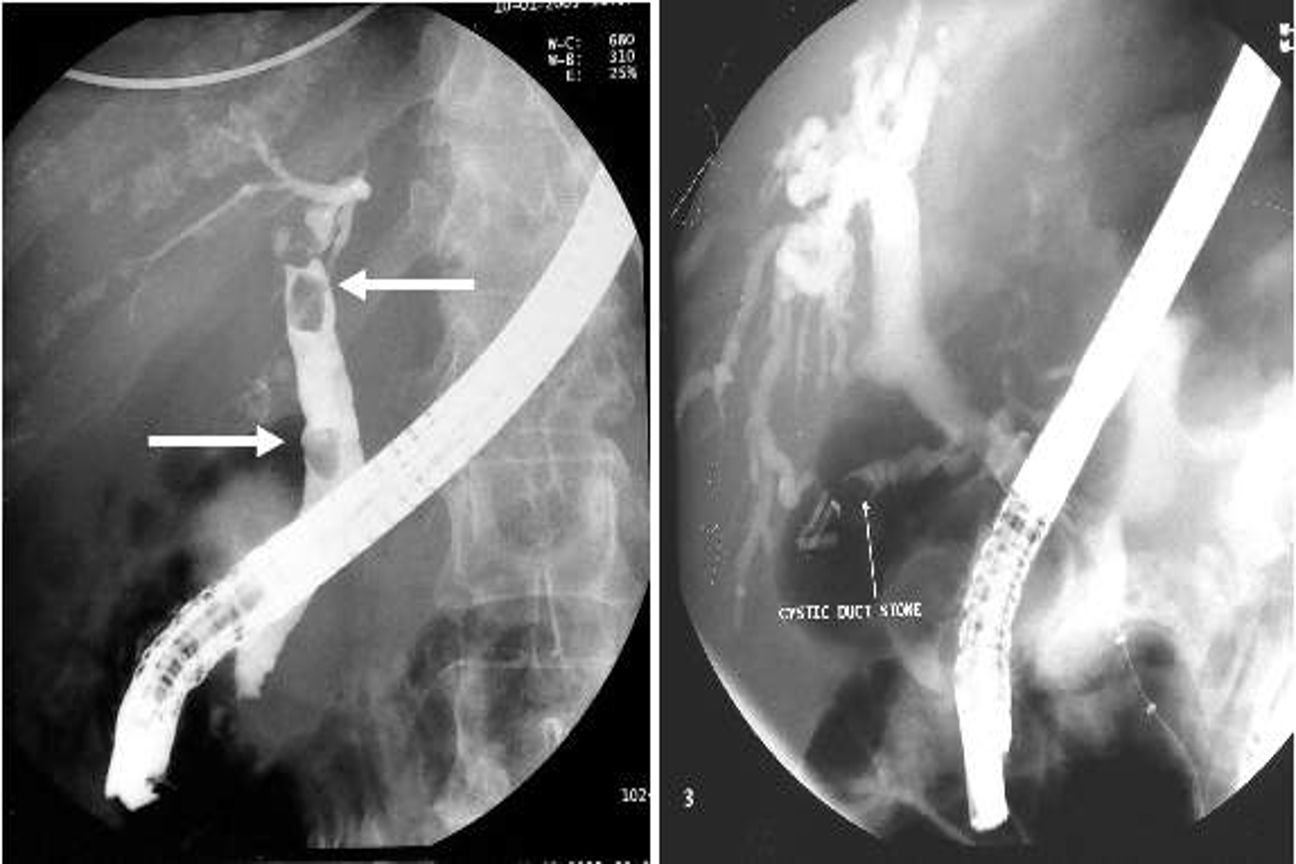

b) Magnetic resonance imaging (MRI): magnetic resonant cholangiopancreatography (MRCP) is non-invasive tool to assess the biliary system. MRI can assess for any lesion causing biliary obstruction such as pancreatic tumor or cholangiocarcinoma.

MRCP showing stone in the common bile duct and in the gallbladder

c) Endoscopic retrograde cholangiopancreatography (ERCP): ERCP is an invasive diagnostic and therapeutic investigation which outline the biliary and pancreatic system by injecting contrast through a cannula inserted into the papilla of Vater by means of side viewing endoscope passed into the duodenum. it gives more detailed information than ultrasound and allows endoscopic extraction of common bile duct stones, biopsy of periampullary tumors, and relief of obstructive jaundice by stent insertion. complications of ERCP included acute pancreatitis, cholangitis, duodenal perforation and bleeding. *NEVER USED IN CASE OF CANCER - COMPLICATED CHOLANGITIS *

ERCP showing stone in the bile ducts

d) Percutaneous transhepatic cholangiography (PTC): it is invasive investigation used to outline the proximal biliary tree in obstructive jaundice by injecting contrast through slim flexible needle passed percutaneously to the liver parenchyma and biliary system.

MRCP study - stone in GB z

Double duct sign and stricture at the lower end of CBD strongly suggest carcinoma of pancreas

-

Note: Double duct sign Z shows that CBD and PD are both dilated

The width of a normal pancreatic duct is 3â4 mm Z

ERCP - CBD Stone

- Sign of filling defect